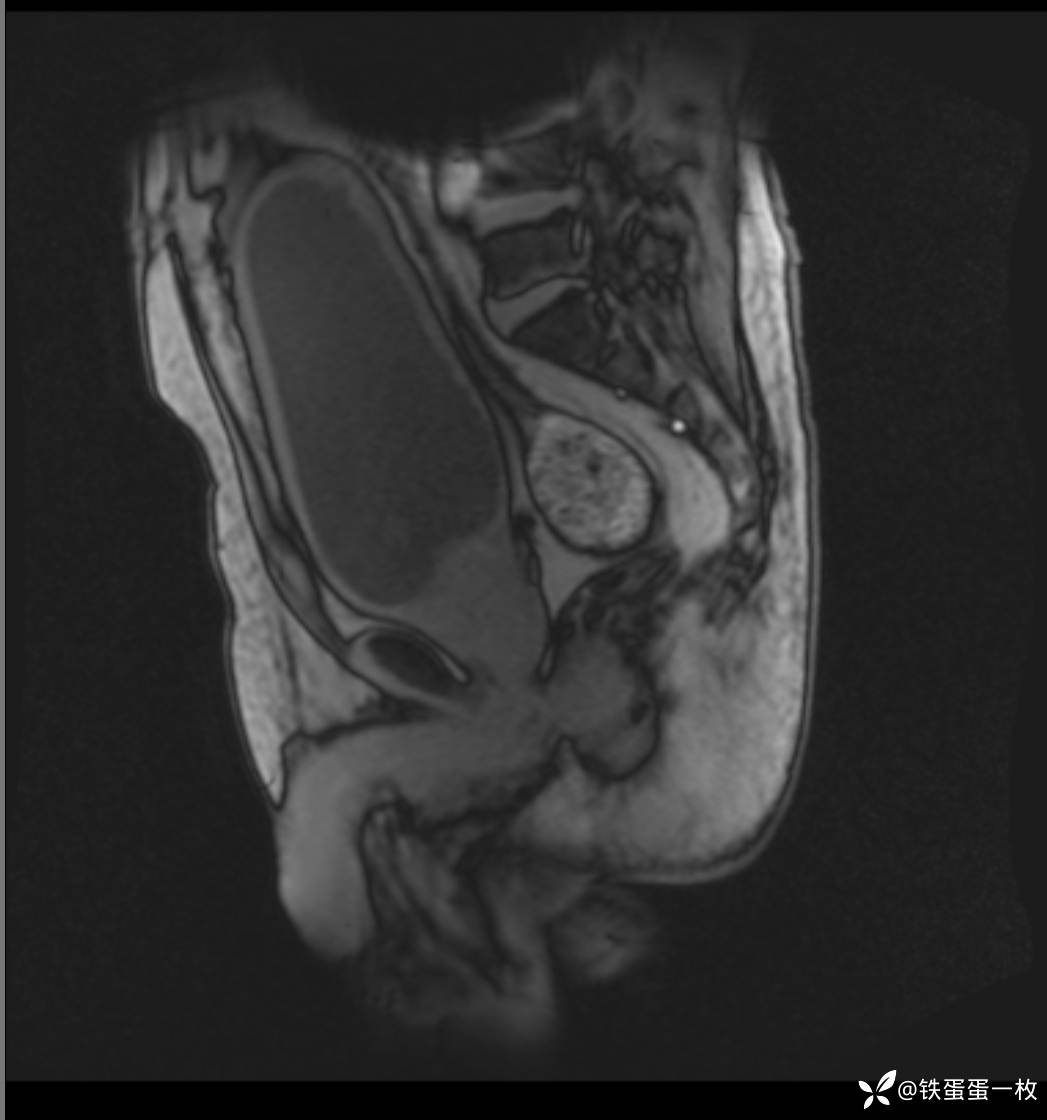

因为前一天晚上彩超、CT都做了,也没查到什么病因,所以直接开了盆腔核磁平扫+DWI+MRU,不一会核磁就打电话来了,说这个病人膀胱上缘周围渗液。你们考虑可能的原因是什么?我说,考虑可能是感染,这个病人既往体健,没有疾病史,昨晚突发血尿,没外伤,也没发现占位、结石,而且抗炎有效,伴有膀胱壁增厚,可能是膀胱炎的可能性大。核磁听了后说他的渗出可多了,给你们传过去看看,于是就有了如下片子↓

2)MRI检查可发现膀胱出现变形,位置上抬,可以对盆腔内脂肪的形状、大小进行较为客观的观测。

矢状位呈“茄形”、“长条形”

膀胱尿道造影:梨形膀胱。(这就是核磁影像后面的图片存在的意义)。